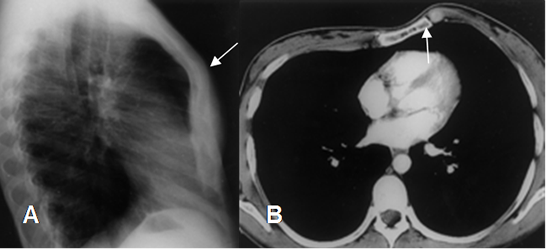

En esta alteración hay desplazamiento anterior del esternón. (4). (Fig 20).

La malformación es menos frecuente que el pectum excavatum y se asocia a enfermedad cardiaca congénita cianosante. (4).

Fig 20. Pectum carinatum.

A: Rx lateral. Aumento del diámetro AP del tórax, con desplazamiento anterior del esternón.

B: TAC axial. Desplazamiento anterior del esternón, por pectum carinatum.